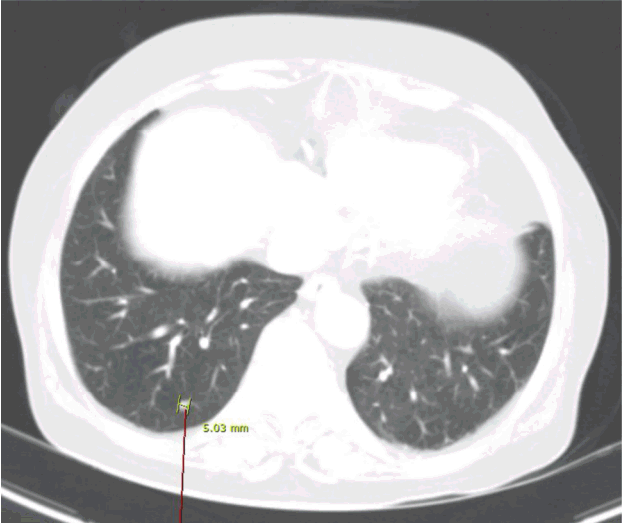

환자: 77세 여자, 경상남도 양산시 거주주소: 3일 전부터 지속된 발열과 전신 위약감현병력: 진드기에 왼쪽 팔을 물려 아들이 진드기를 제거하였다고 하며 진드기에 물린 후 6일째부터 발열이 있었고 8일째에 발열, 전신 위약감으로 본원 응급실을 내원하였다.과거력: 고혈압직업력: 농사신체 검사 소견: 혈압 100/60 mmHg, 맥박수 93회/분, 체온 39.3℃, 호흡수 19회/분으로 전신 위약감이 있었으나 의식은 명료하였다. 결막은 창백하지 않았고 공막은 황달 소견을 보이지 않았고 두경부 림프절은 만져지지 않았다. 흉부 청진상 폐음은 깨끗하였고 복부 검진상 복부 팽창은 없었고 만져지는 종물이나 압통은 없었고 장음은 정상이었다. 하지부종은 관찰되지 않았다. 진드기에 물린 자리는 가피 등 별다른 이상 소견은 보이지 않았다.검사실 소견: 말초 혈액 검사 소견은 백혈구 1,300 μL, 혈색소 11.3 g/dL, 혈소판 84,000 μL였다. 혈청 생화학 검사에서 아스파르테이트아미노전달효소(AST) 127 IU/L, 알라닌아미노전달효소(ALT) 43 IU/L, 젖산탈수소효소(lactate dehydorgenenase) 734 IU/L, 혈액요소질소 23.9 mg/dL, 크레아티닌 1.07 mg/dL, C-반응성단백 0.29 mg/dL, 크레아틴인산화효소(creatine kinase) 1,513 U/L였다. 나중에 orientia tsutsugamushi Ab (blood) 양성(320×), 페리틴(ferritin) > 8,000 ng/mL, 트리글리세리드(triglyceride) 1,887 mg/dL, 피브리노겐(fibrinogen) 242 mg/dL, soluble interleukin-2 receptor 1,020 U/mL (일본 Life Science Institute Medience에서 시행한 검사 결과), Epstein-Barr virus anti-viral capsid antigen IgM (blood) 음성(0.04)으로 나왔다. NK 세포활성도(NK cell activity)에 대한 검사는 시행하지 않았다.영상 검사 소견: 전산화단층촬영상 양폐 하부에서 5 mm 결절이 여러 개 보이고 신장문 높이의 대동맥 근처에 중심괴사를 동반한 조영 증가되는 2.4 cm 종괴가 관찰되었다(Figs. 1 and 2).기관지내시경 소견: 특별한 endobronchial lesion은 관찰되지 않았으며 right middle lobe에서 bronchoalveolar lavage을 시행하였다. 검사상 cell count 330, neutrophil 27%, lymphocyte 39%, monocyte 34%로 나왔으며 배양 검사, acid fast bacilli 농축 염색, M. tuberculosis polymerase chain reaction (PCR), respiratory virus PCR 등에서 특별히 검출된 것은 없었으며 병리 검사에서도 악성 세포는 보이지 않았고 반응성 변화(reactive change)의 가능성이 높은 것으로 보고되었다.골수 검사 소견: 과립세포성 과증식을 동반한 대략 40%의 세포성 골수와 독성 변화를 보였으며 거핵세포 수는 적절하나 조직구 수는 증가되어 있으며 특히 혈구 탐식 조직구(CD3:-,CD20:-,CD68:+)가 발견되어 혈구탐식성 림프조직구증(HLH) 소견을 보였고 임상 양상과 CT 소견을 고려하여 림프절 종양을 의심하였으나 이후 SFTS virus 양성으로 나와 결과적으로 감염과 관련된 혈구탐식성 림프조직구증(HLH)으로 나왔다(Fig. 3). SFTS virus 양성 판정은 질병관리본부에 급성기 때 혈액 샘플을 보내서 real time reverse trasncription PCR을 통해서 M7 segment Gn gene의 viral RNA를 증폭하여 확진 검사를 시행하였다.치료 및 경과: 발열, 전신 위약감 등으로 환자 내원하여 시행한 검사상 백혈구 감소증, 혈소판 감소증, 빈혈, 간효소단백의 상승 소견 및 전산화단층촬영상 신장문 높이의 대동맥 근처에 중심 괴사를 동반한 조영 증가되는 2.4 cm 종괴가 관찰되어 림프종을 의심하여 호중구 감소성 발열에 대해 항생제(piperacillin + ciprofloxacin)를 사용하면서 골수 검사 고려하에 입원하였다. 입원 후 orientia tsutsugamushi Ab 양성(320×) 소견으로 나왔고 동시감염 또는 위양성 의심되었지만 배제할 수 없어 doxycyclin을 추가하여 사용하였다. Orientia tsutsugamushi Ab titer를 추적 검사하여 수치 변화를 확인하는 것이 동시 감염 또는 위양성 등의 감별에 도움이 줄 수 있을 것으로 생각되나 그 당시에 추적 검사를 하지 않은 점은 감별진단을 함에 있어 부족한 점으로 생각된다. 골수 검사 결과상 혈구탐식성 림프조직구증(HLH) 및 림프절 종양 의심 소견이었으나 이후 SFTS virus 양성으로 나와 항바이러스제(리바비린[ribavirin] 4 g/d)를 추가하였으며 의식 저하 등 환자 상태가 더 악화되면서 승압제, dexamethasone (HLH-2004 치료지침에 기준하였으며 인공호흡기, continuous renal replacement therapy 적용 중이어서 에토포시드 적용은 어려울 것으로 판단), 인공호흡기, 지속적 신대체 요법까지 적용하였으나 다발성 장기부전으로 결국 입원 22일째 사망하였다.

중증열성혈소판감소증후군(SFTS)는 버냐바이러스 과(Bunyaviridae family), 플레보바이러스 속(Phlebovirus genus)에 속하는 SFTS virus에 의해 매개되는 감염병으로 작은소피참진드기(Haemaphysalis longicornis)에 물렸을 때 감염되는 것으로 알려져 있다[1]. 진단은 SFTS virus의 분리, 급성기에 SFTS virus RNA의 검출, 회복기에 SFTS virus에 대한 혈청 IgG 항체가 급성기에 비해 4배 이상 증가된 경우 또는 혈청 전환의 탐지 중에 한 가지 이상일 경우 진단할 수 있다[1]. 현재까지 중증열성혈소판감소증후군에 대한 효과적인 치료는 명확하지 않으나 리바비린(ribavirin)이나 인터페론(interferons)이 도움을 준다는 보고도 있고 사망률에 큰 차이를 보이지 않는다는 보고도 있다[3,4].또한 중증열성혈소판감소증후군이 있는 환자에서 림프절 종대가 나타나는 빈도를 고찰해보면, Yu 등[1]의 논문에서 81명의 환자 중에 23명(33%), Liu 등[4]의 논문에서 311명의 환자 중에 132명(42.4%)에서 림프절 종대가 나타났으며 이는 중증열성혈소판감소증후군이 있는 환자에서 림프절 종대가 관찰될 가능성이 있음을 알려주며 이에 대해서 앞으로 더 많은 사례와 기전에 대한 연구가 필요할 것으로 생각된다. 이 환자의 경우에 림프절 종대가 있어 처음에 림프종을 의심하였으므로 림프종과의 감별을 위해 조직검사가 필요했으나 환자 상태가 조직검사를 하기 어려운 상태여서 시행하지 못했기 때문에 림프절 종대가 중증열성혈소판감소증후군에서 나타났을 가능성이 높겠지만 림프종의 가능성을 완전히 배제하기는 어려울 것으로 생각된다. 폐에서 발견된 결절의 경우에는 중증열성혈소판감소증에서 나타날 수 있는 병변인지에 대해 명확히 발표된 다른 논문을 찾을 수 없었으며 우연히 발견된 양성 병변이나 실제로 관련이 있을 가능성 등을 생각하여 앞으로 중증열성혈소판감소증에서 폐결절이 있는 사례에 대한 연구가 필요할 것으로 생각된다.혈구탐식성 림프조직구증(HLH)은 성인의 경우에 여러 가지 요인에 의해 체내 면역기전이 활성화되었다가 신호 전달의 이상으로 비활성화가 되지 못해 계속적인 면역 세포의 자극으로 정상 세포를 공격하여 장기부전을 일으키고 분비된 사이토카인들이 염증 반응을 일으키게 되는 질환이다[5]. 진단은 HLH-2004에 따르면 골수나 비장 또는 임파선에서 혈구탐식증(hemophagocytosis)의 발견, 38.5℃이상의 열이 7일 이상 지속, ferritin ≥ 500 mcg/L, soluble CD25 (sIL-2 recepter) ≥ 2,400 U/mL, 비장 종대, NK세포활성도가 정상치보다 낮은 경우, cytopenia가 2계통 이상인 경우(Hb <9 g/L, PLT < 100 × 109/L, absolute neutrophil count < 1.0 × 109/L), 고중성 지방혈증(fasting triglycerides ≥ 265 mg/dL) 또는 저섬유소혈증(fibrinogen ≤ 1.5 g/L) 이상 8개 기준 중 5개 이상일 경우이고[6] 치료는 종양, 감염, 류마티스 질환 등 다양한 원인 질환에 대한 교정 및 면역억제제(사이클로스포린, 덱사메타손)와 세포독성항암제(에토포시드) 등이 고려된다[5-8].골수 검사에서 나온 혈구탐식성 림프조직구증 소견은 SFTS virus 양성 소견과 연관하여 감염과 관련된 혈구탐식성 림프조직구증으로 생각되었는데, 앞서 기술한 바와 같이 종양, 감염, 류마티스 질환 등 다양한 원인이 있겠지만 진드기에 물리고 나서 열이 나는 등 환자 병력과의 관련성을 고려해 볼 때 SFTS virus 감염으로 인한 가능성을 크다고 보았다. 물론 림프종에 대한 조직검사가 필요했으나 환자 상태로 인해 하지 못한 점은 림프종을 완전히 배제하지 못하는 제한을 가진다.